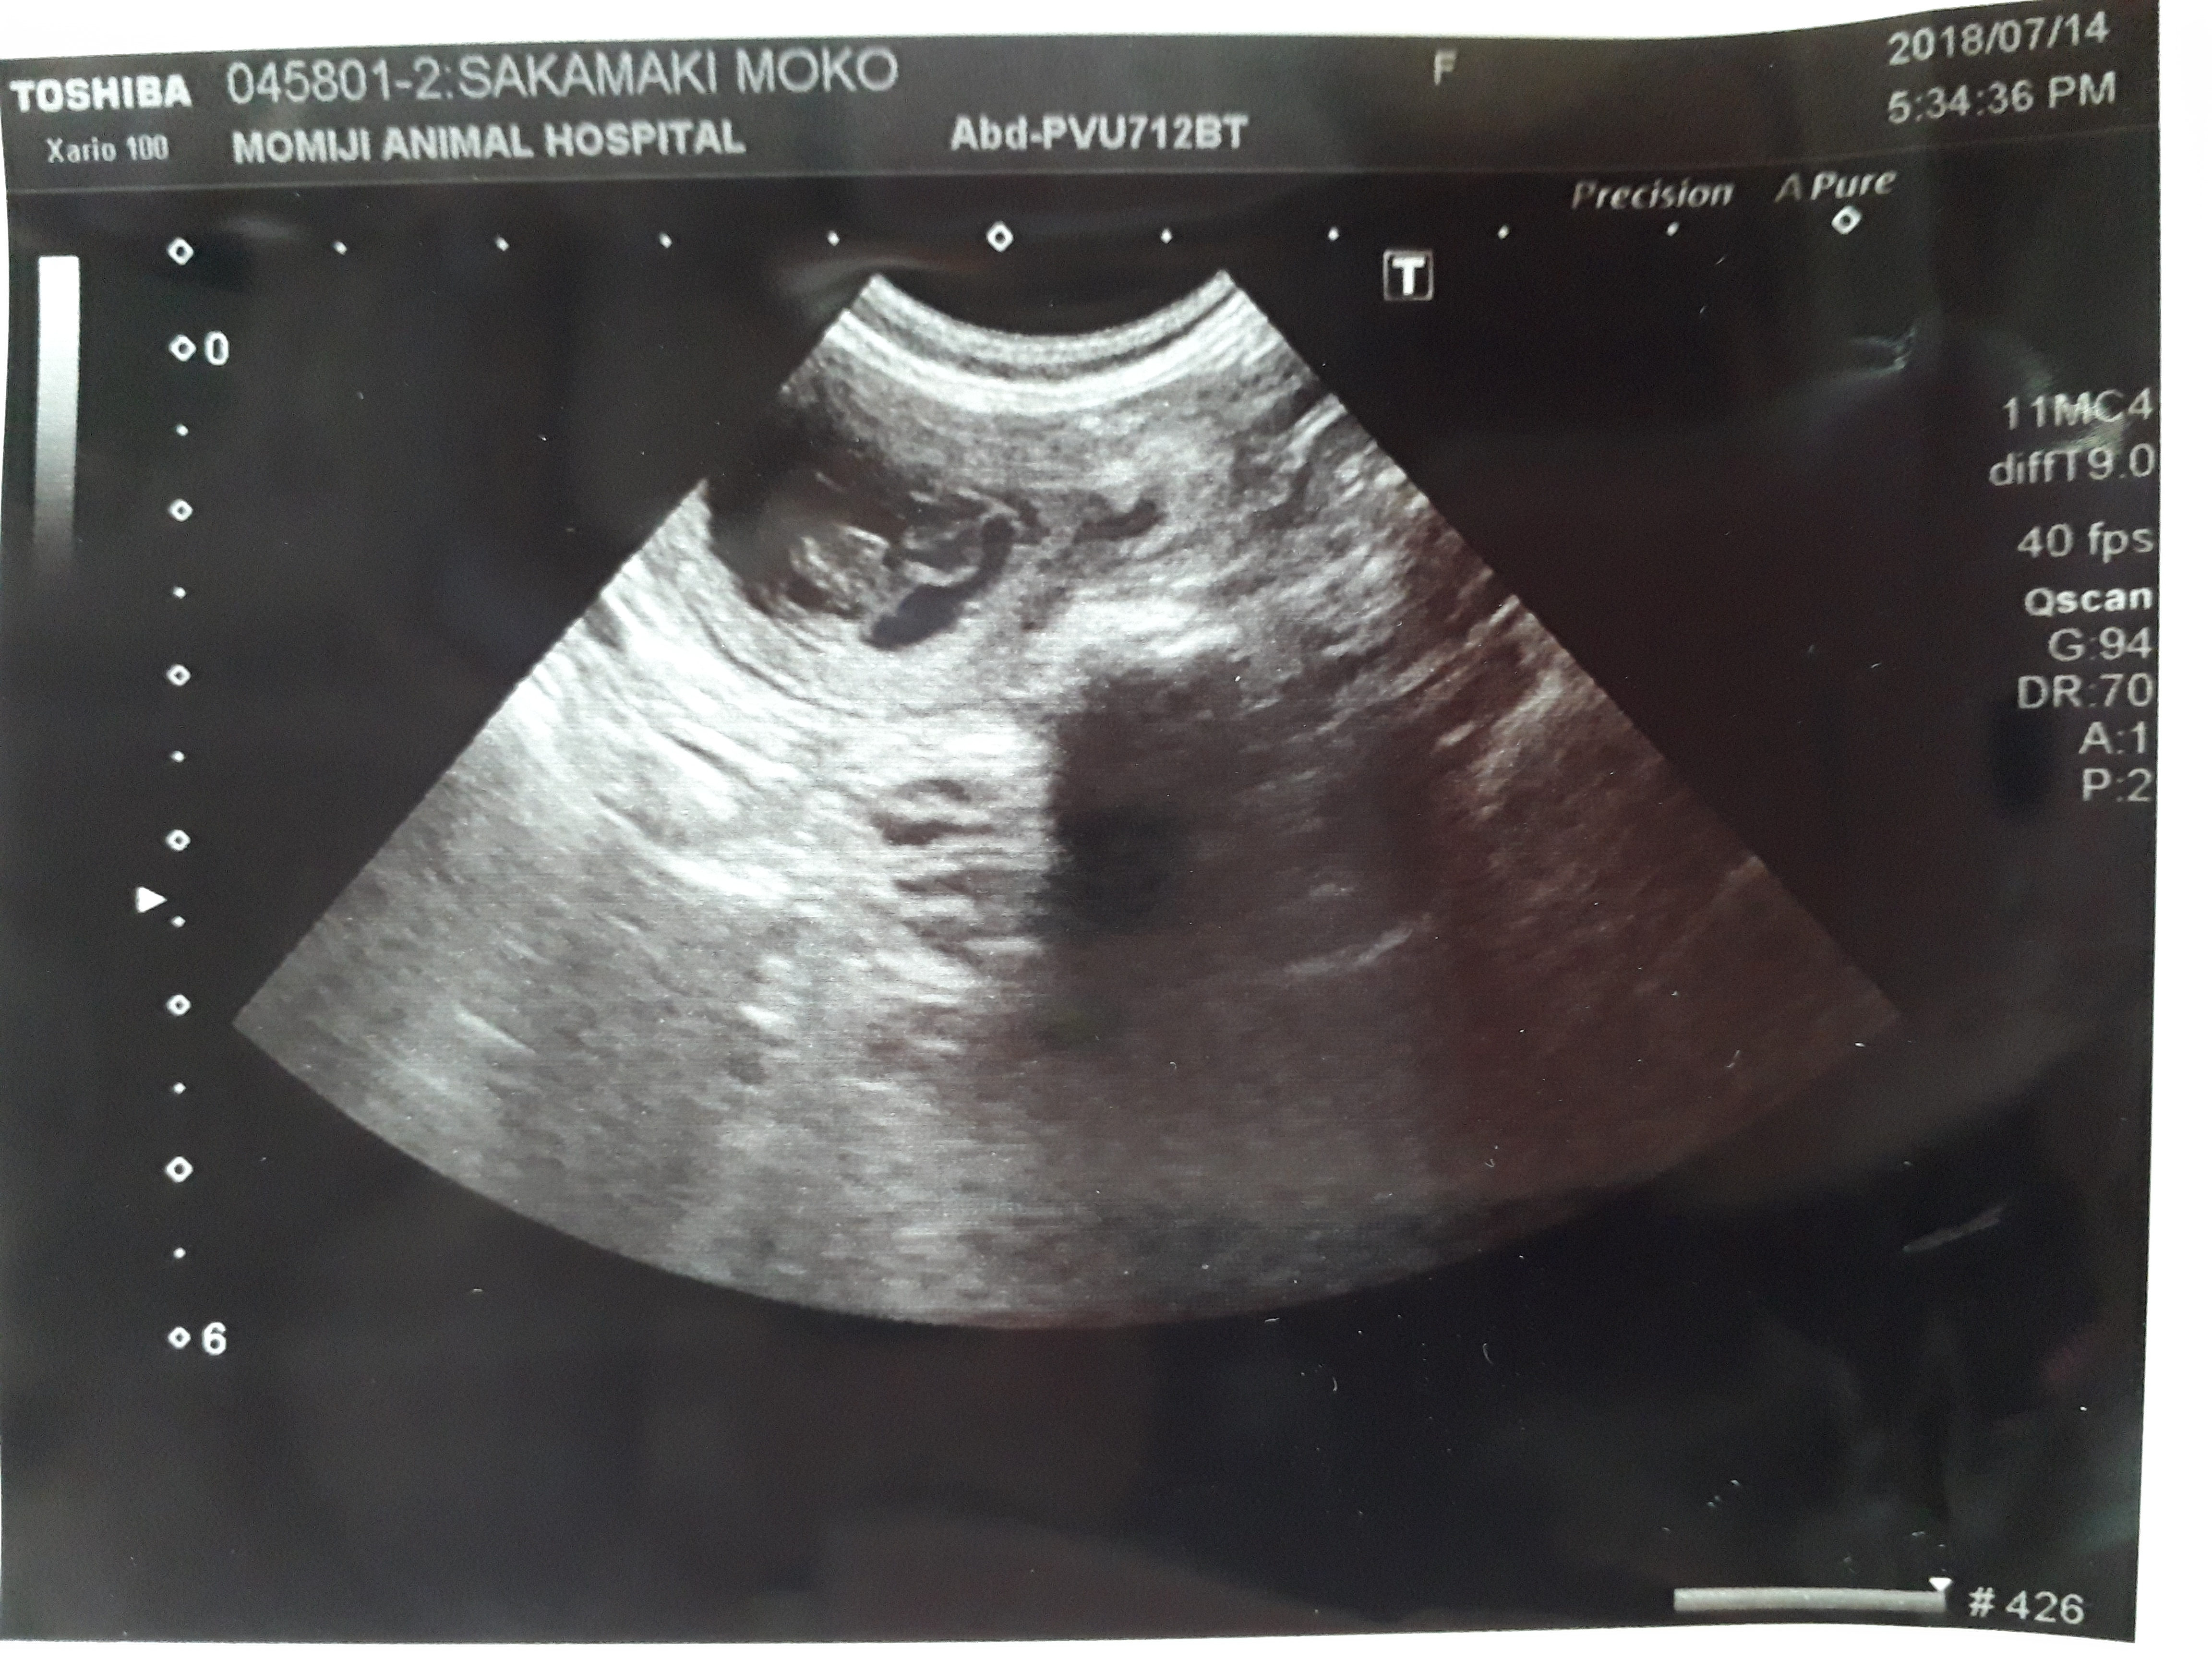

H30.8.11妊娠56日目になりました。 出産予定日が近づいてきましたので、お産室を組立てました。 当犬舎のお産室は、母犬のストレスを少なくするため、母犬が自由に出入りできる仕組みになっています。 また、母犬がお産室を自由に出入りできることで、母犬は日常的に使用しているトイレ(お産室の外のトイレ)で用を済ませることができますので、お産室を清潔な状態で保つことができます(^^)v ※写真と動画は昨年のものです。 |